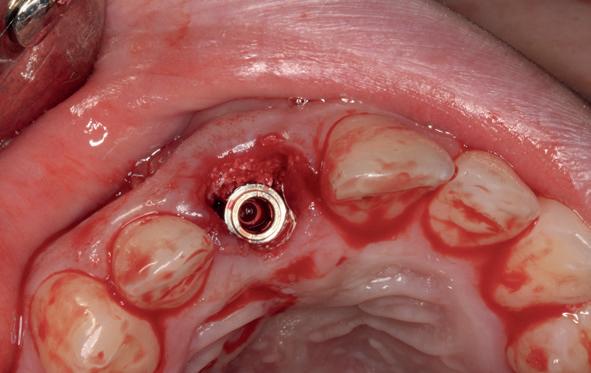

Afbeelding 1 en 2. Een immediate placement (afbeelding 1) is maar weinig invasief en zal weinig nalast geven. Bij een uitgebreide botopbouw (afbeelding 2) daarentegen is de wond veel groter en kan er meer nalast verwacht worden.

In deze casus is extractie van de 37 geïndiceerd in verband met een fistel en restpockets, zoals zichtbaar op de röntgenfoto’s (afbeelding 1). Duidelijk te zien is de forse peri-apicale ontsteking en het botverlies bij de 37, dat zowel richting buccaal als linguaal doorloopt. De 37 wordt atraumatisch verwijderd. Er is aan de linguale zijde veel bot verloren en er is sprake van een perforatie aan de buccale zijde.

Er wordt besloten om botmateriaal te plaatsen in de extractie-alveole. Vervolgens wordt het afgesloten met een titanium versterkt d-PTFE membraan (afbeelding 2). Na vier weken wordt het membraan verwijderd.

Zes maanden na extractie wordt het implantaat 37 geplaatst. Er is sprake van een goede genezing en de processushoogte en -breedte zijn behouden en opgebouwd. Ook is er zichtbaar gekeratiniseerd weefsel

gewonnen. De wond kan na het plaatsen van een healing abutment primair gesloten worden (Afbeelding 3a-3d).